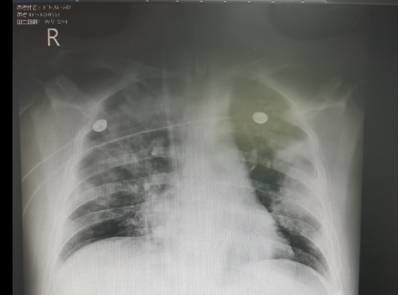

8mm磨玻璃结节的治愈率受结节性质、肿瘤生物学行为等多因素影响,纯磨玻璃结节中良性病变经有效治疗治愈率较高,部分实性磨玻璃结节中早期肺癌相关结节经规范手术治疗预后较好但个体因多种因素有差异,总体无统一精确数值需综合多方面因素具体评估每个患者的治愈率情况。